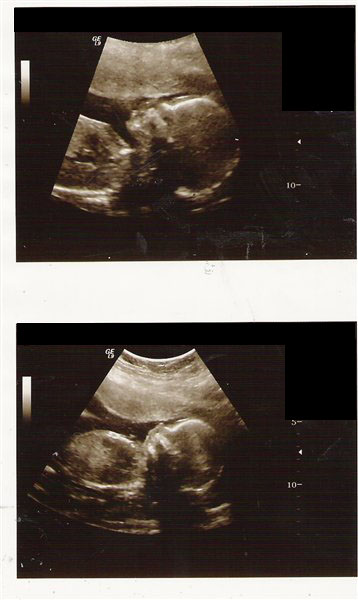

Åh, hvor godt at han har det fint derinde...spændende med tiden, den går jo hurtigt og lige om lidt er han ude hos dig:9